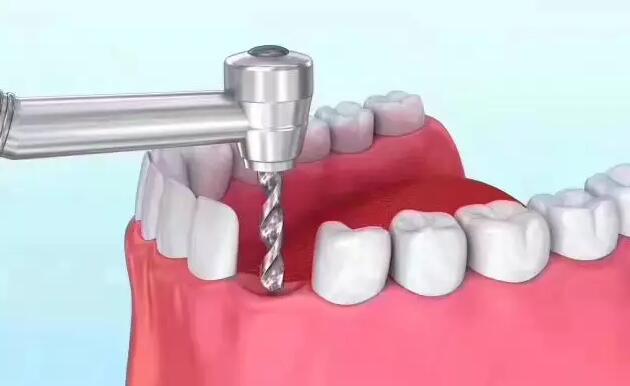

种植牙对于各种牙齿缺失问题都能够进行有效的修复,具有美观度好,咀嚼功能强大,舒适度好的优势,因此很多人选择通过种植牙来修复牙齿的缺失,今天就带大家一起了解下口腔种...